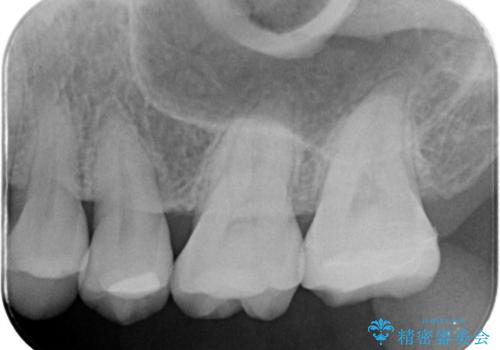

- 主訴:左上の銀の詰め物、笑うと見えそうで気になるので白くしたい。

保険適応のメタルインレーが入っていたため、適合性・審美性の良いセラミックインレーでのやり替えとなりました。

保険適用のメタルインレーを除去したところ、歯質との境目部分にカリエスを認めたため、カリエス除去しCR裏層の後、セラミックインレーを形成しました。